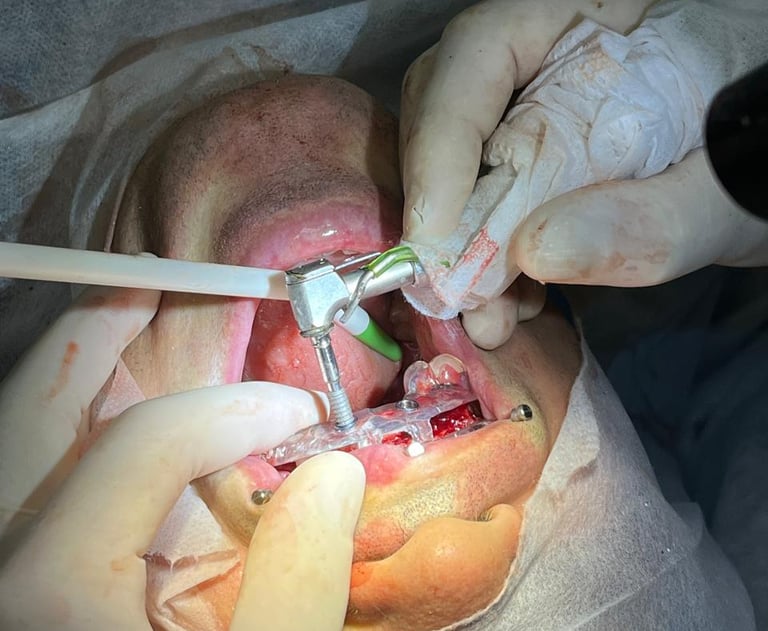

Cirurgia Guiada

Utilizamos a cirurgia guiada para instalação de implantes, garantindo resultados eficazes, minimamente invasiva, maior precisão, menor tempo cirúrgico, maior conforto pro paciente e menor sangramento.

Com a tecnologia da cirurgia guiada em implantes dentários, o tratamento é feito de forma planejada e precisa. O uso de softwares digitais garante o posicionamento ideal dos implantes, reduzindo riscos, tempo de cirurgia e proporcionando um pós-operatório mais confortável.

Cirurgia Guiada com Guias Empilháveis (Stackable Guide)

A técnica de cirurgia guiada com guias empilháveis (Stackable Guide) é uma inovação na implantodontia, proporcionando mais precisão, previsibilidade e segurança nos procedimentos

Consiste em um sistema de guias cirúrgicas que se sobrepõem (empilháveis), permitindo um planejamento digital detalhado e uma execução mais precisa da cirurgia

🔹 Maior estabilidade e controle durante a perfuração e colocação dos implantes

🔹 Redução do tempo cirúrgico e pós-operatório mais confortável para o paciente

🔹 Minimiza cortes e suturas, tornando o procedimento menos invasivo

🔹 Melhor adaptação das próteses devido ao planejamento digital

Essa técnica é ideal para casos complexos e reabilitações extensas, garantindo um alto nível de precisão e previsibilidade para o sucesso do tratamento.